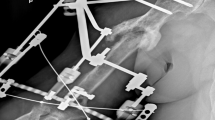

After the surgery, the ring of the excised anorectal mucosa was cut open and flattened on a surgical towel as shown in Fig. 2. The presence of muscle in the specimen was confirmed grossly and photographed. The entire surface area of the mucosa, muscle and the muscle/mucosa ratio were measured by the surgeon using the ImageJ software (National Institutes of Health, Bethesda, MD, USA).